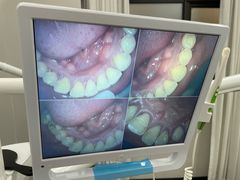

• 牙博士口腔品牌连锁(杨浦店)

• -牙博士口腔品牌连锁(杨浦店)

忠诚贤明咔嚓虾 | 22-08-11